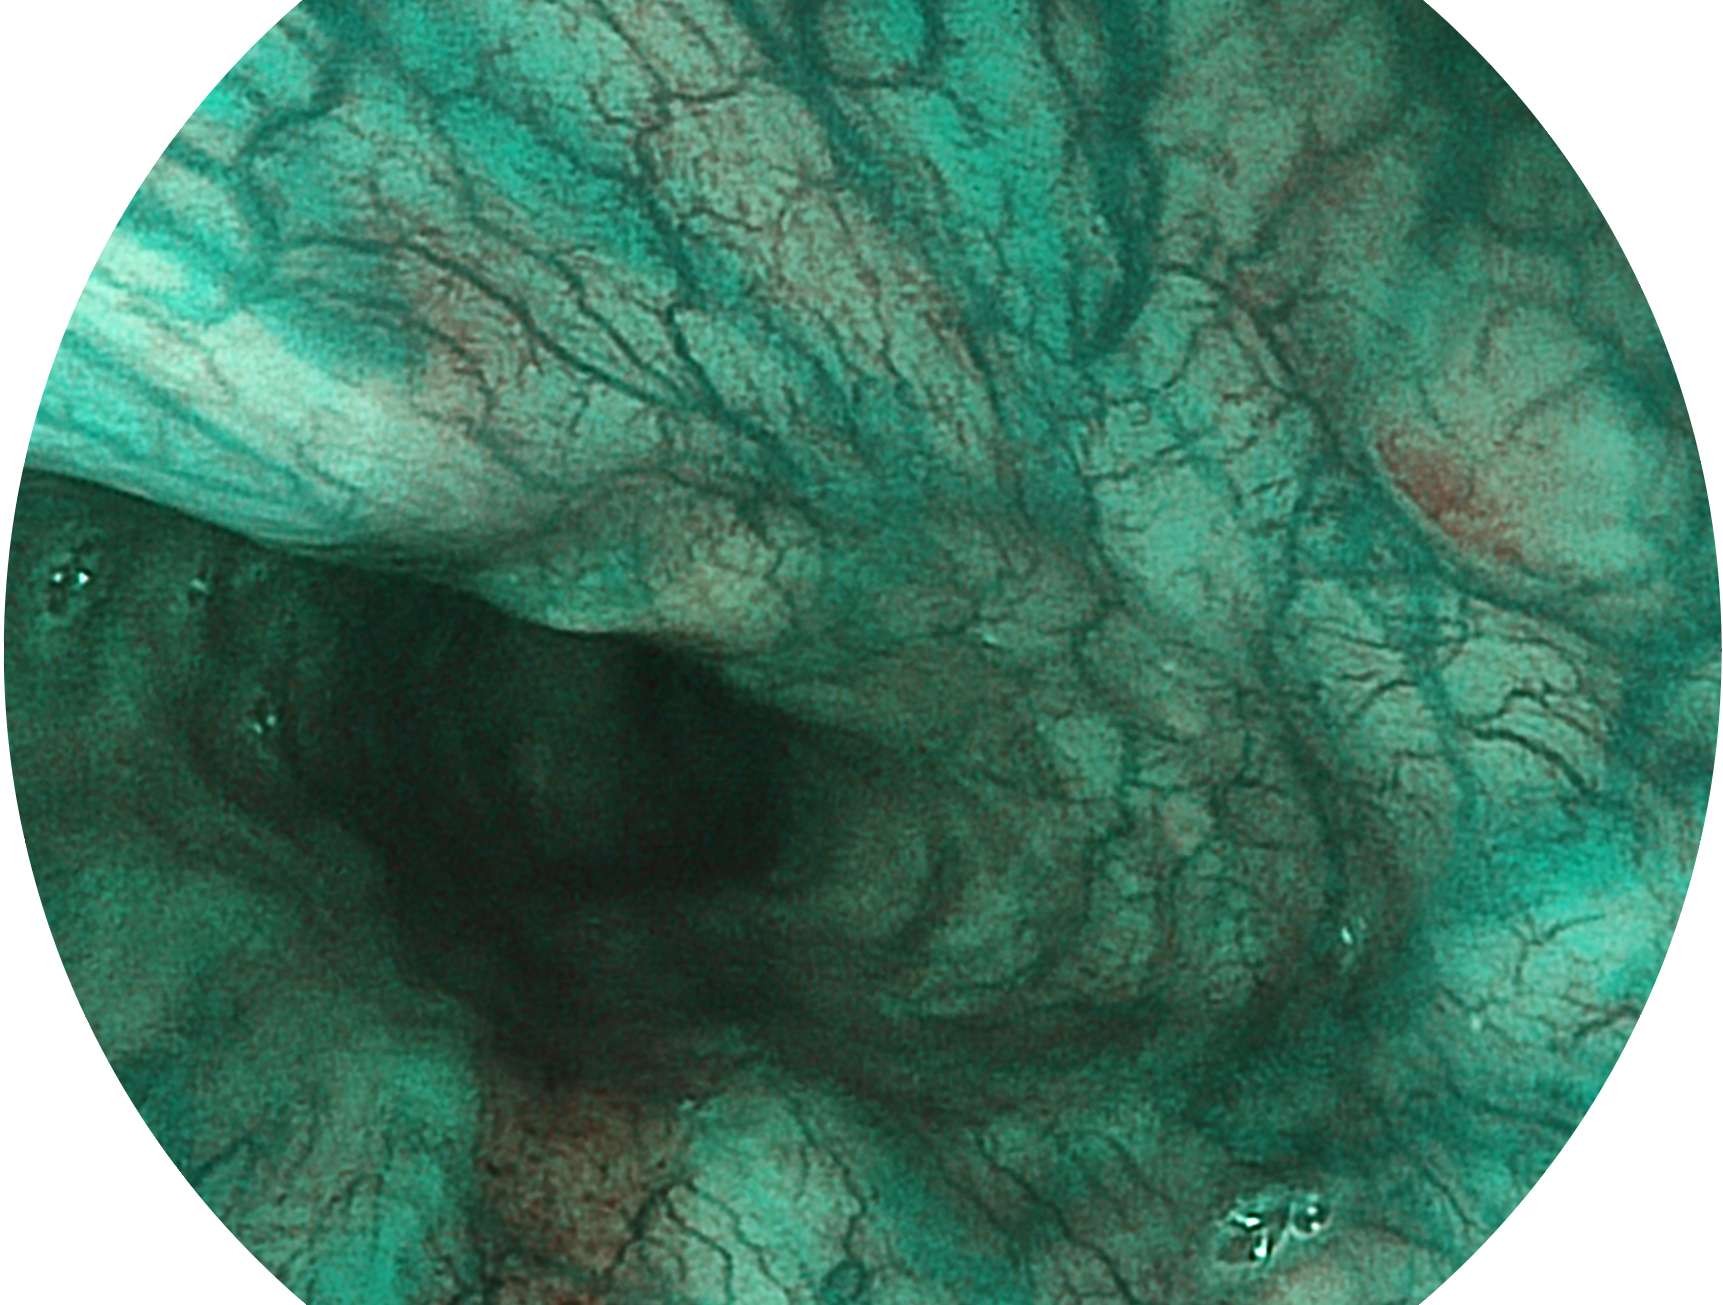

新葡的京集团8814检测站新开发的内镜染色技术,主要是基于多波长LED 光源的开发,VLS-55Q 四波长LED 光源是由四个不同颜色的LED光按照相应照明模式所规定的特定发光比例进行合束后形成,合束后形成的照明光的光谱由红光、绿光、蓝光及蓝紫光这四个不同的波段范围构成。具有更高光谱自由度,通过光谱比例的控制,实现了聚谱成像技术,英文全称为“Spectral Focused Imaging, SFI”,缩写为“SFI”和光电复合染色成像技术,英文全称为“Versatile Intelligent Staining Technology, VIST”,缩写为“VIST”。